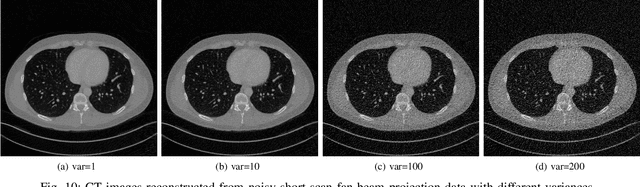

Abstract:A CT image can be well reconstructed when the sampling rate of the sinogram satisfies the Nyquist criteria and the sampled signal is noise-free. However, in practice, the sinogram is usually contaminated by noise, which degrades the quality of a reconstructed CT image. In this paper, we design a deep network for sinogram and CT image reconstruction. The network consists of two cascaded blocks that are linked by a filter backprojection (FBP) layer, where the former block is responsible for denoising and completing the sinograms while the latter is used to removing the noise and artifacts of the CT images. Experimental results show that the reconstructed CT images by our methods have the highest PSNR and SSIM in average compared to state of the art methods.